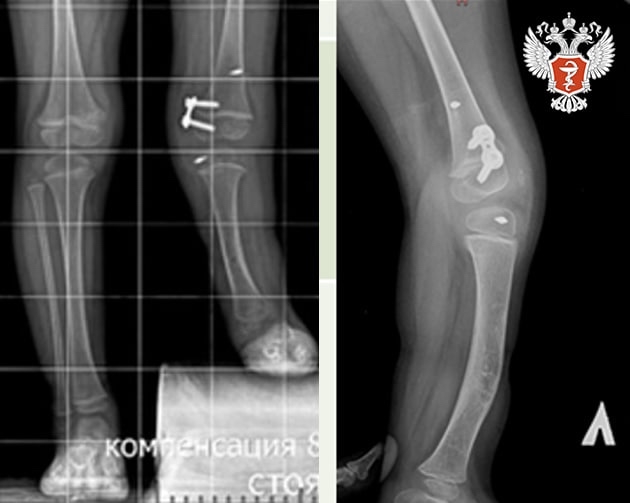

↪️ Первую операцию одной из пациенток провели, когда ей был год: тогда врачи реконструировали голень и стопу. Это позволило ребенку ползать, вставать и ходить. В два года девочке провели операцию на коленном суставе и стабилизировали сустав. Это предотвратило смещение голени перед последующим удлинением ноги.

↪️ Сейчас пациентка снова поступила в НМИЦ травматологии и ортопедии им. ак. Г. А. Илизарова Минздрава России на повторную операцию двухуровневое удлинение большеберцовой кости аппаратом Илизарова. На данном этапе будет увеличена длина ножки на 6 см. В процессе роста девочки планируется несколько этапов удлинения конечности с интервалом в 3 года.